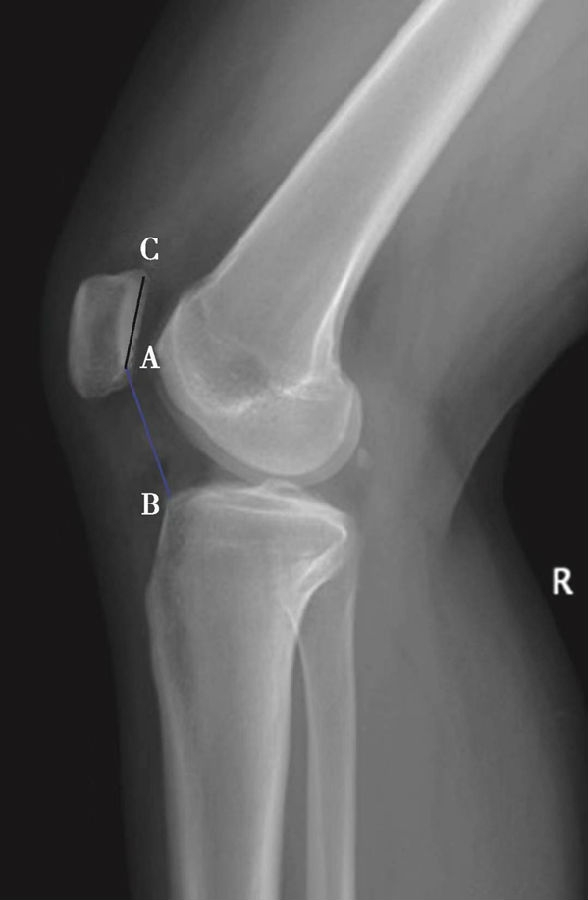

如图示:AB是髌韧带长度,AC髌骨纵轴长度。Insall-Salvati指数=AB/AC(图4)。

图4 Insall-Salvati指数 =AB/AC=1.10,为正常髌骨高度

图5 Insall-Salvati指数=AB/AC=1.40,为高位髌骨

但是此法测量髌骨韧带时往往依赖准确的估计胫骨结节与髌骨下极的位置。因此,髌骨下极和胫骨结节的病变都会影响测量的结果,尤其是发生胫骨结节骨软骨炎的患者确定这一位置便更加的困难。此外,该指数不能用于评估胫骨结节向近端或远端移位的效果。因为该指数测量所使用的标记在胫骨结节术后均未发生改变,Insall指数也就不会变化。